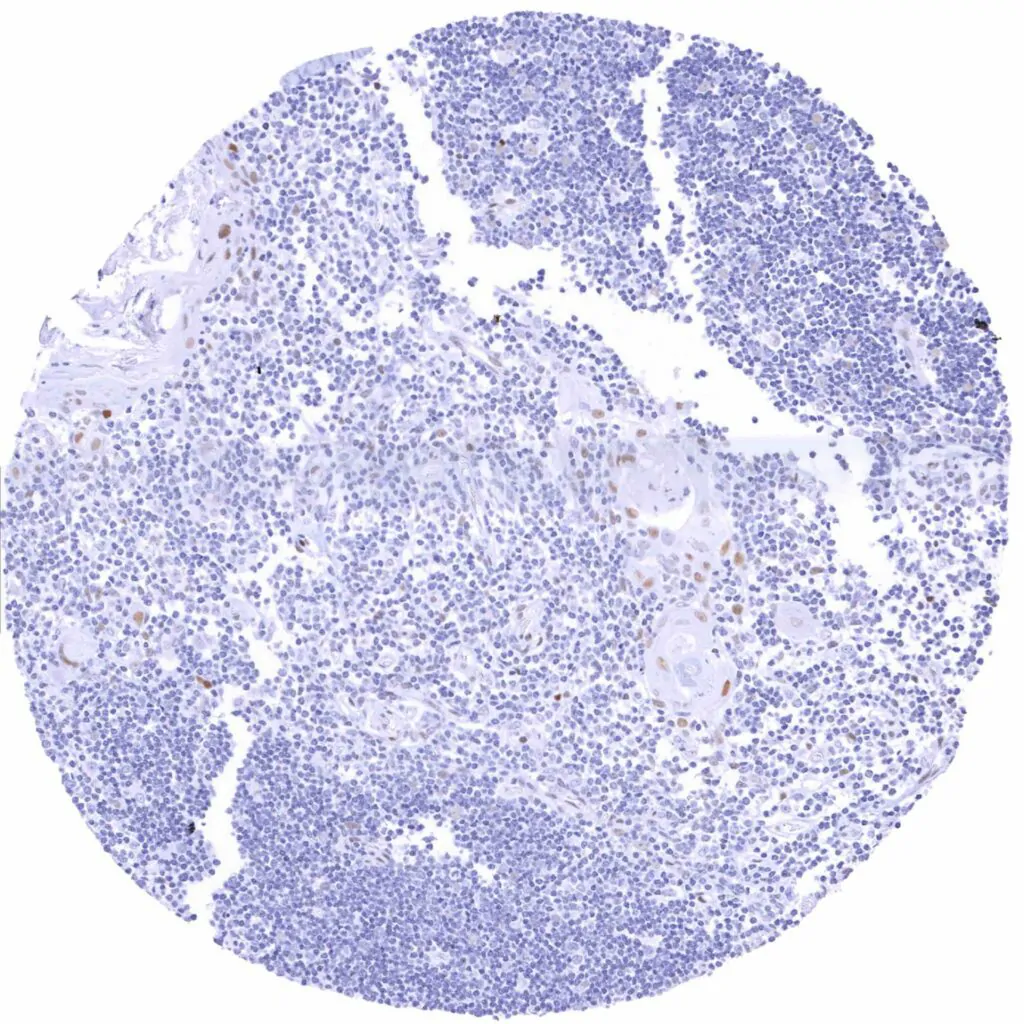

Lymph node – Weak to moderate TLE1 staining in a subset of lymphocytes, predominantly in germinal centres